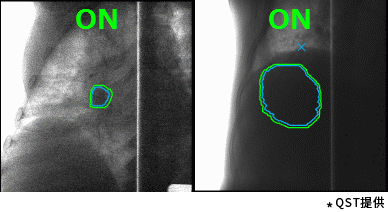

东芝的重离子癌症放射治疗系统具有高速3D扫描,患者自动定位,小型化重离子旋转机架(搭载东芝自研超导磁铁实现重量和体积的大幅缩小)等差异化技术。实时成像的呼吸门控是照射技术与重复扫描技术的结合,能够对伴随呼吸运动的肿瘤进行快速、准确的照射,且保证剂量分布均一性。特别是,东芝凭借自身先进的超导技术的加持,使旋转机架得以逐渐小型化。这一成果直接推动了重离子旋转机架的商业化普及。应用旋转机架治疗,可从360度任意角度进行照射,避开正常组织和危及器官。治疗过程中一次定位,避免了移动患者造成的内部脏器位移,实现精准治疗,同时提高治疗效率,增加治疗人数,在同类型产品中独具技术优势。

高速扫描+呼吸门控照射(动图) |